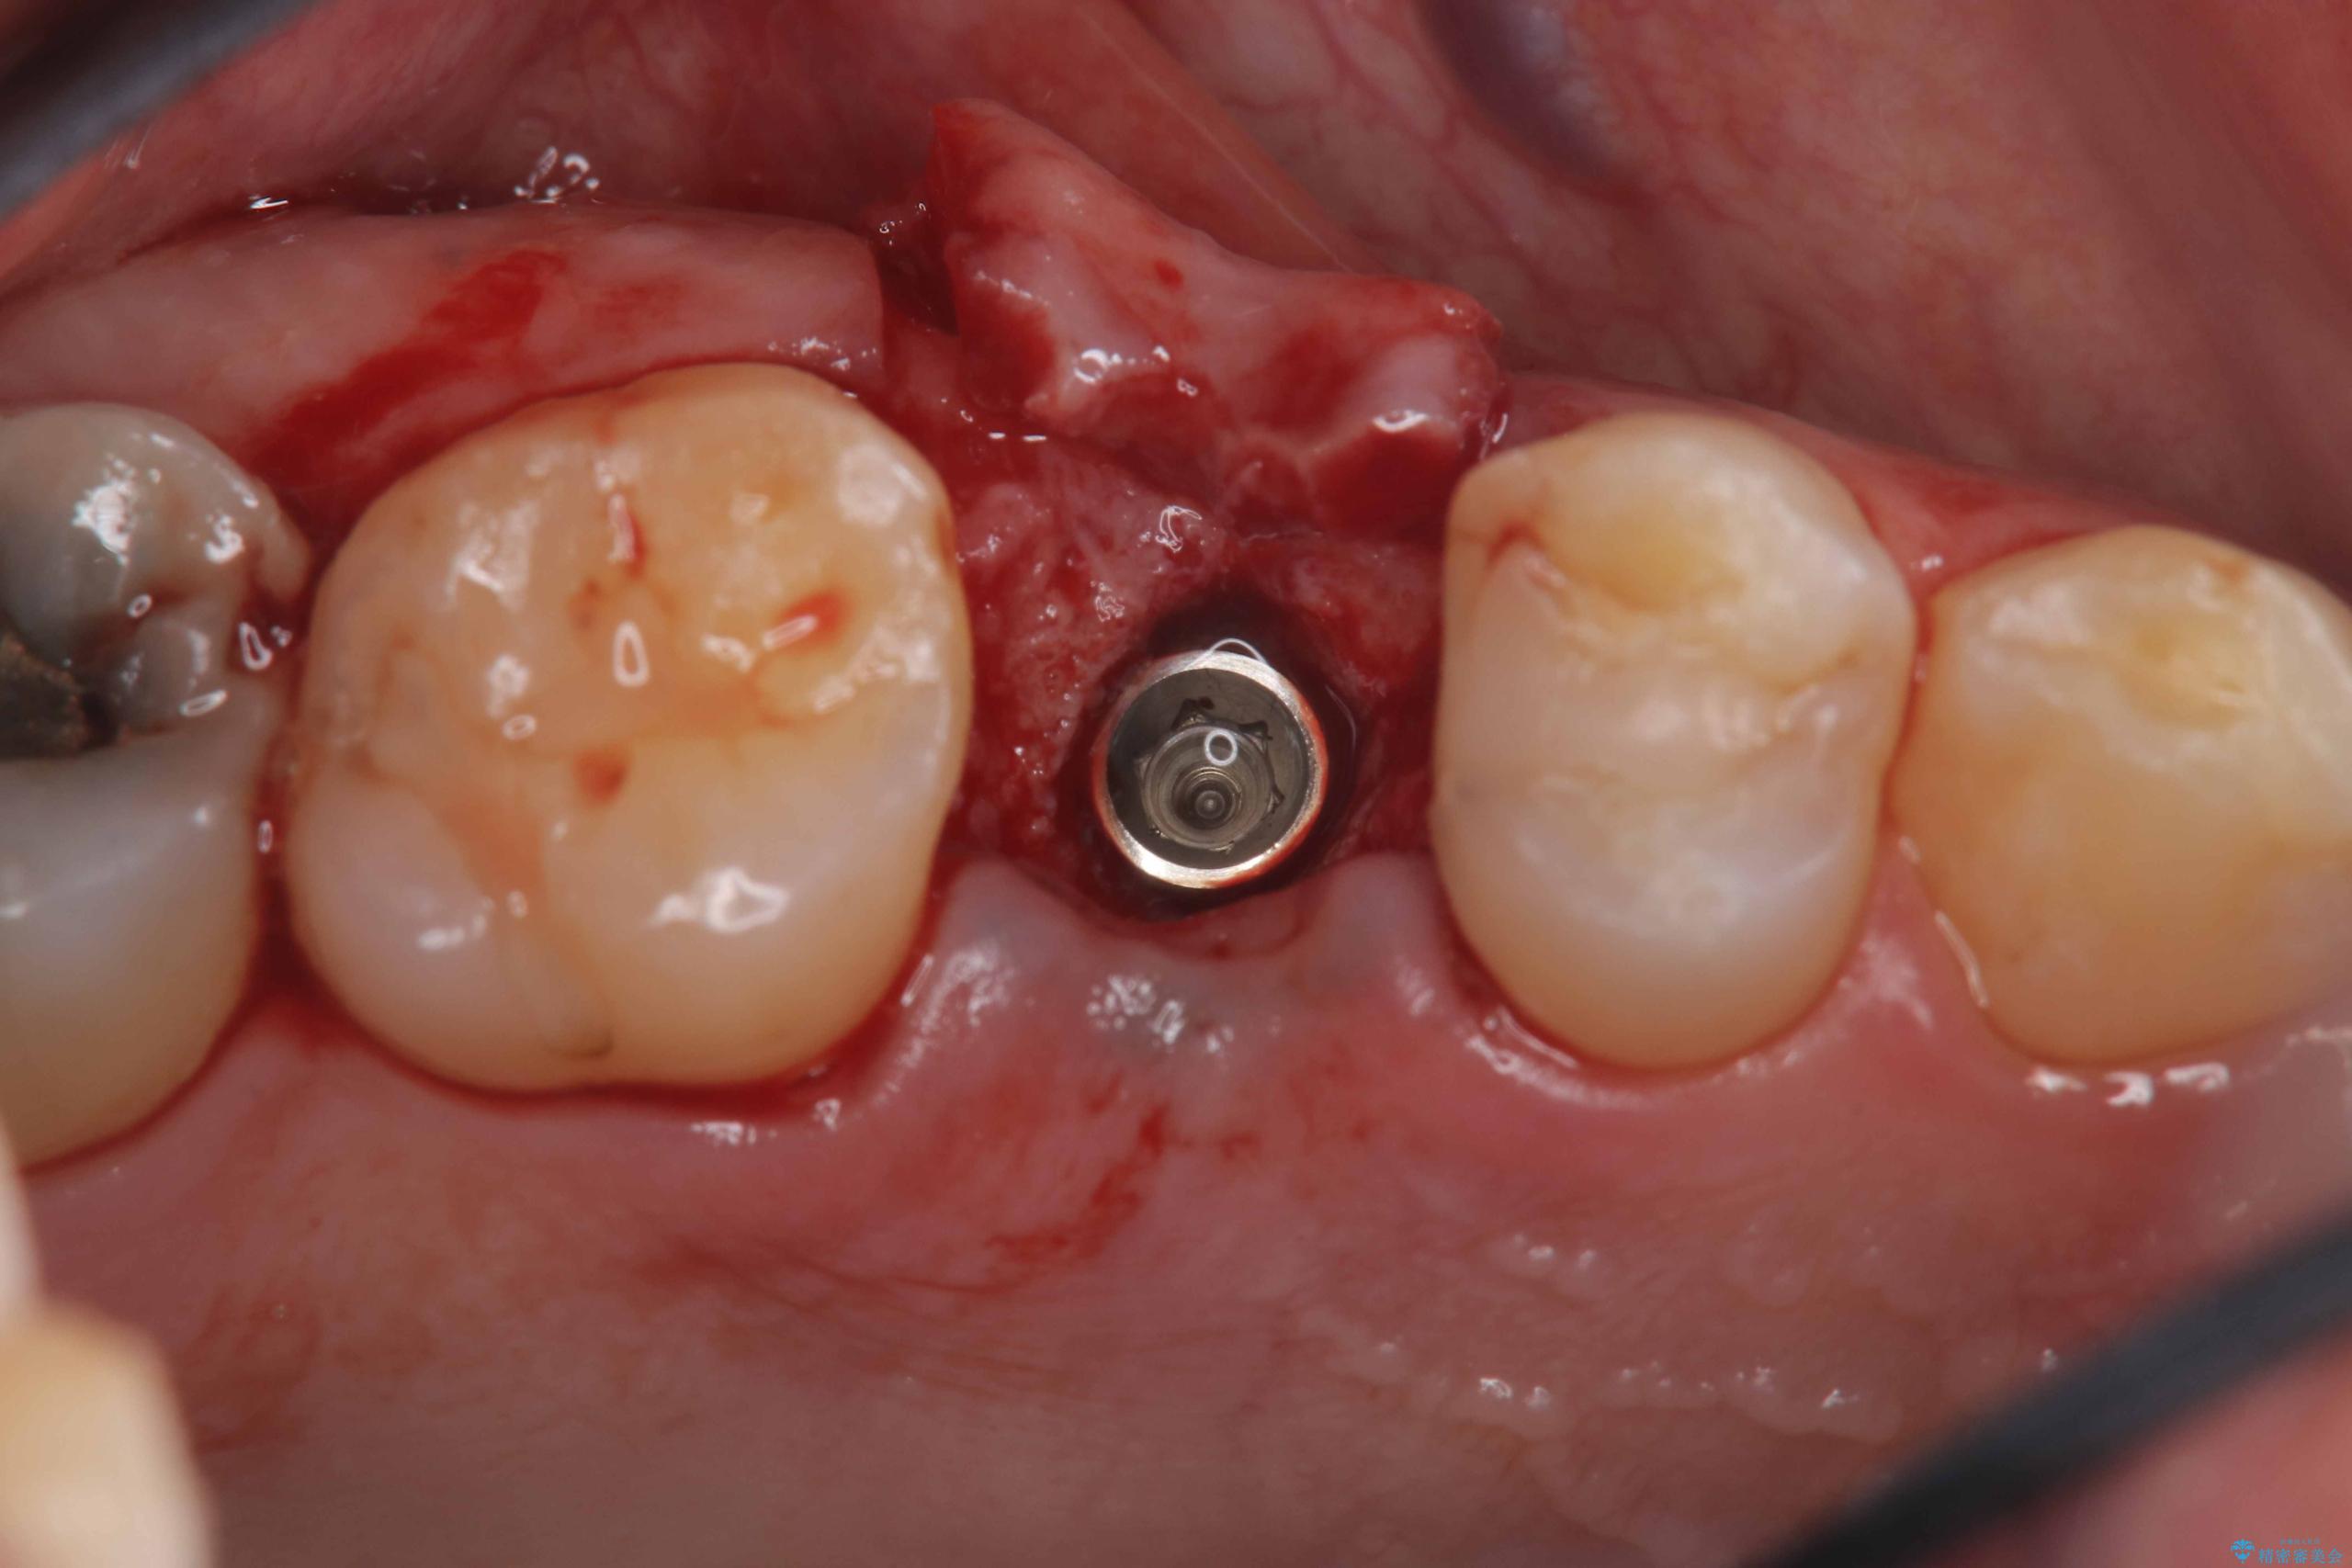

右上5番が根尖性歯周炎と歯周病が同時に併発しており、骨が大きく溶け、歯の動揺も著しかったため保存困難と判断をし抜歯してインプラントで治療を行いました。

インプラントはインプラント周囲炎になりにくいスクリュータイプを使用しています。

従来のインプラント治療では、オペを二回に分けることが主流でしたが今は1回のオペで治療を終える事が出来るようになりました。

インプラントと骨が強度にくっつくように骨密度を上げながらドリリングを行っているのと、患者様の骨の状態に合わせてインプラントの形態を選ぶことで可能となっています。